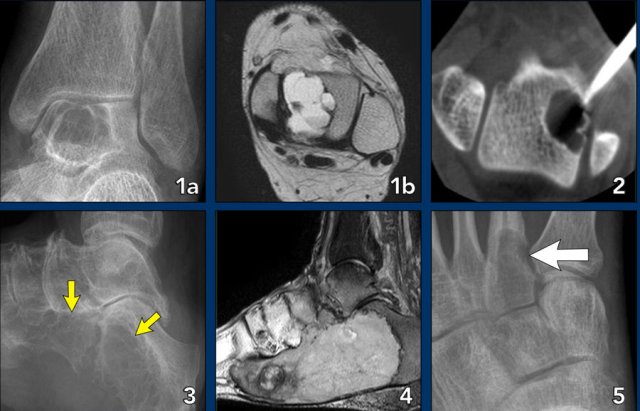

Foot lesions

Here some typical examples of bone tumors in the foot:

- Geode or subchondral cyst in the navicular bone

- Geode or subchondral cyst in the tarsal bone

- Chondroblastoma in the tarsal bone

- X-ray and MRI of a chondroblastoma in the tarsal bone

- Aneurysmal bone cyst in the tarsal bone

- Chondromyxoid fibroma (CMF) in the calcaneus

- Same patient MRI

- CMF in the second metatarsal bone

- Ewing sarcoma in the calcaneus

- Glomus tumor